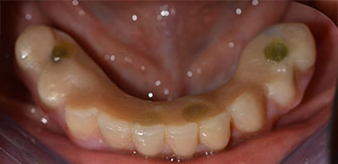

The mental foramen was first identified as a limiting anatomical structure and then the cortical bone of the crest was smoothed with the straight handpiece and a large rose-head bur (Fig. 4).